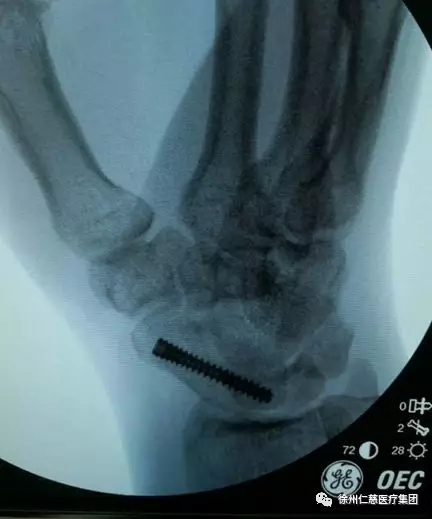

首先,齐主任先将患者的左侧患肢放在侧台上,用牵引架和指套牵引着,沿左手腕背侧切开长约0.5cm的皮肤切口,用关节镜探查发现左舟状骨骨折端稍错位。

手术完左腕后,同术式对患者的右腕舟骨骨折部位进行复位固定。